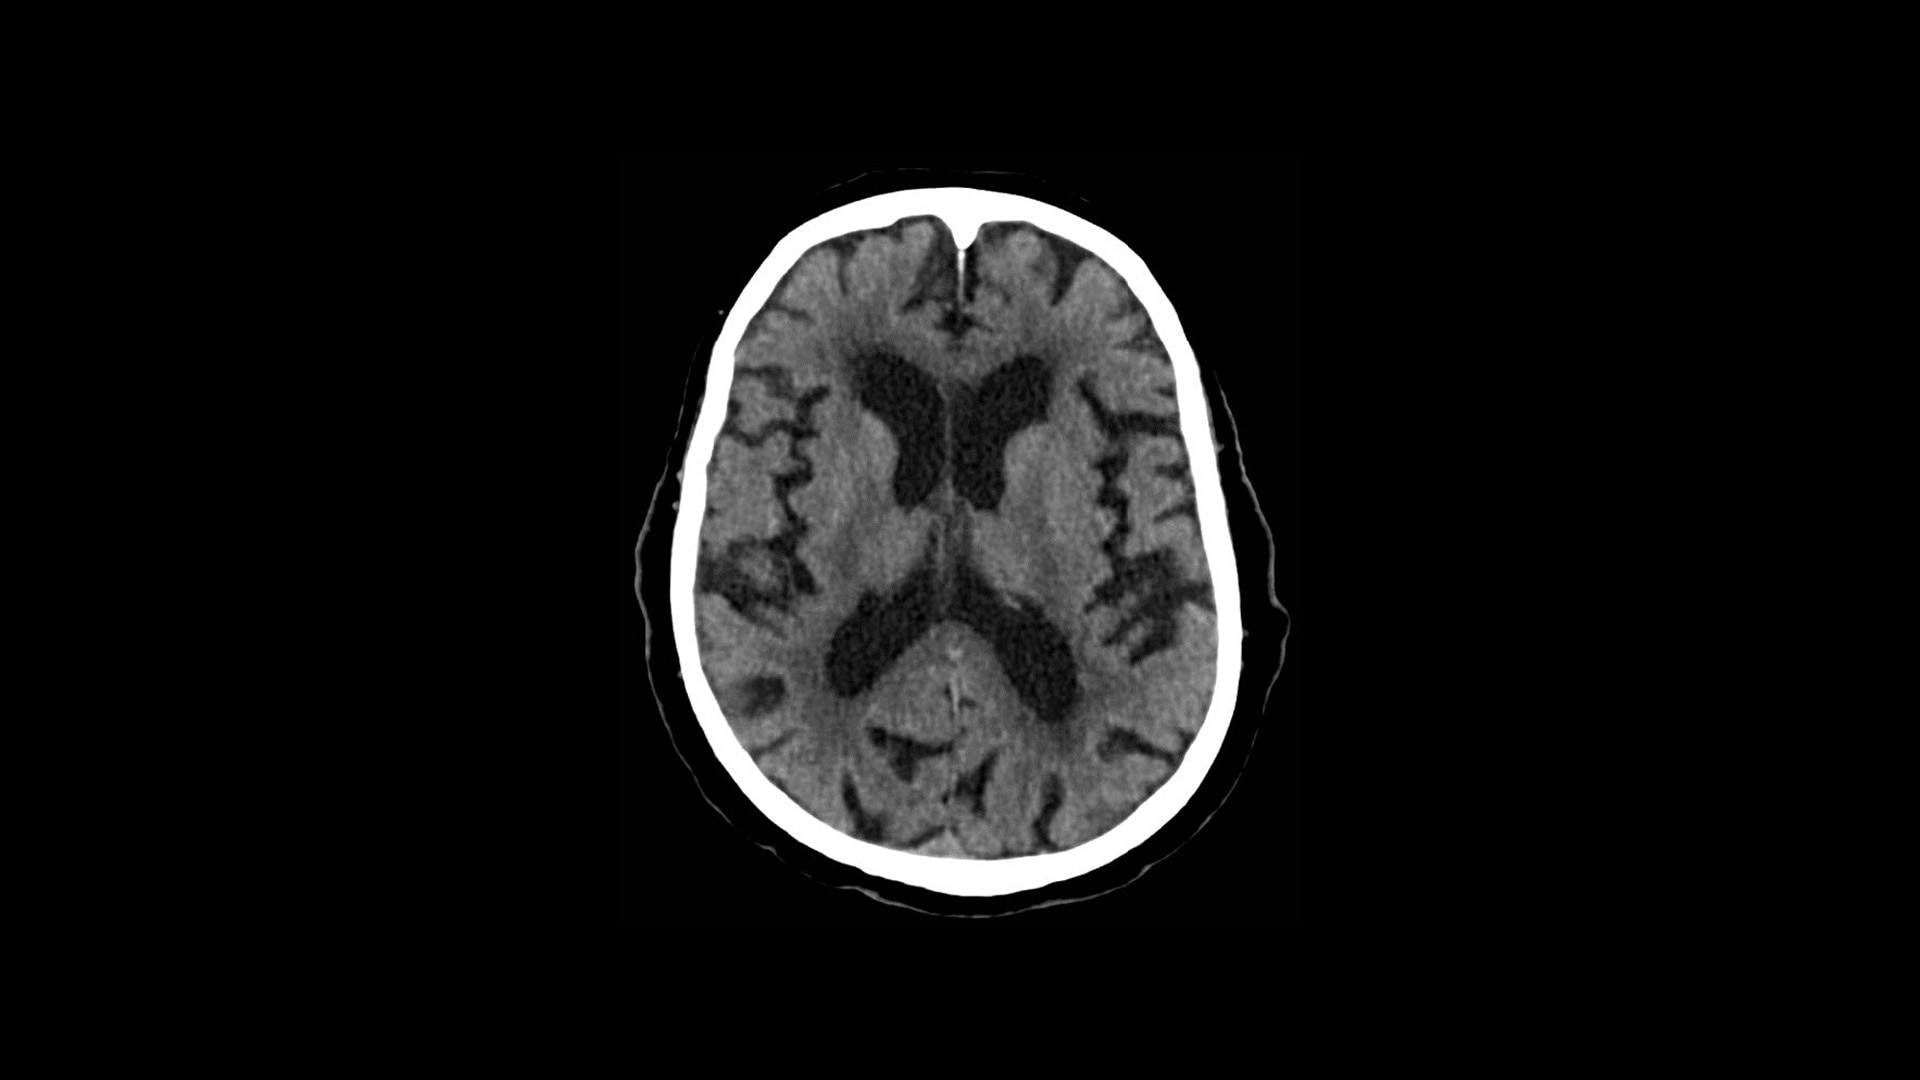

Effortless Workflow

Simplified scanning from start to finish

Available on all Revolution Ascend Platform configurations, Effortless Workflow intelligently automates your CT workflow from pre-scan protocoling to post-scan processing. It uses AI-based features to help transform the entire CT experience and provides maximum efficiency, accuracy, clarity and consistency.

This enables technologists to automatically and accurately personalize scans for each patient with significantly less effort. The end result is a beautiful CT image acquired in less time.